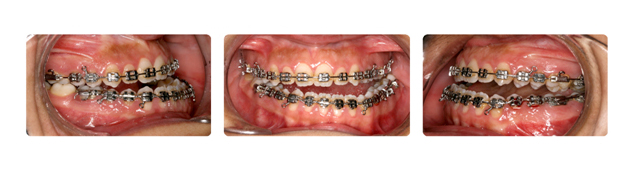

| دندانهای فک بالا و پایین دارای بی نظمی میباشند و با توجه به نبود فضا, بدون کشیدن دندان و توسط سیستم دیمون درمان میشوند: |

![]() |

| درمان با براکتهای دیمون نتیجه بخش است: |